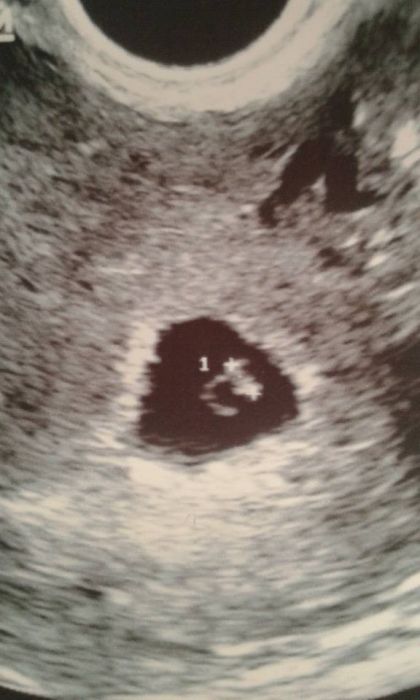

Ahoj holky tak ja pridavam fotecku uz nam krasne tluce srdicko podle ms 5+6tt a podle utz 6+0tt